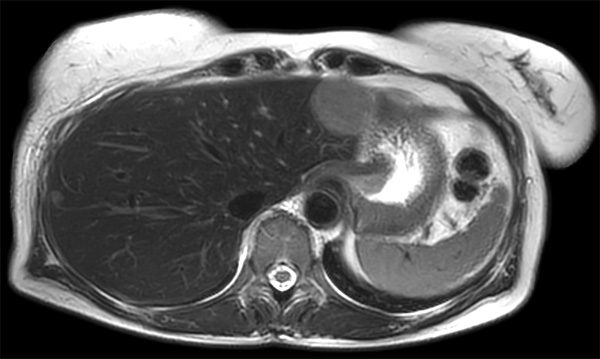

Patient with multiple liver lesions showing up hyperintense on T2-weighted images. The high spatial resolution of MultiVane XD can be appreciated by comparing the images demonstrating the two hyperintense focal liver lesions. mDIXON Quant was performed for quantification of intralesional and hepatic parenchymal fat content. The fat content in the liver parenchyma was normal. The lesion has a fat fraction of 25-30%. Histopathologic diagnosis was hepatocellular adenoma.